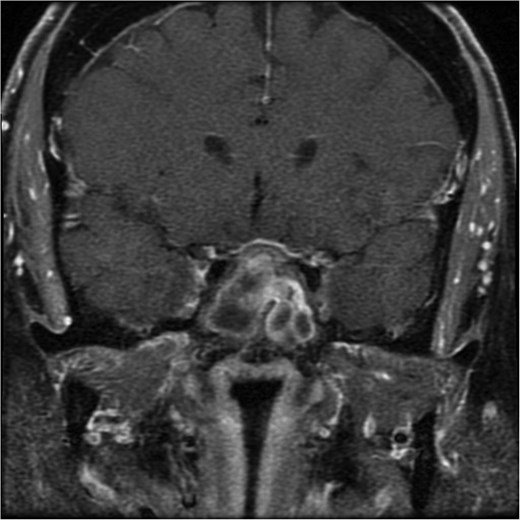

The initial evaluation included a brain magnetic resonance imaging (MRI), showing a small pituitary mass measuring 1.3 × 2.1 × 1.9 cm with suprasellar extension, neighboring the optic chiasm (Figs 1 and 2). Laboratory results revealed a high prolactin level of 110 ng/ml and normal thyroid function tests. A pituitary macroadenoma, specifically a prolactinoma, was presumed, and cabergoline was initiated.

A coronal brain MRI showing a heterogeneous, enhancing lesion located within the sphenoid sinus, extending superiorly to the sellar and parasellar regions. The mass shows irregular borders and appears to cause a mild compression of the optic chiasm.